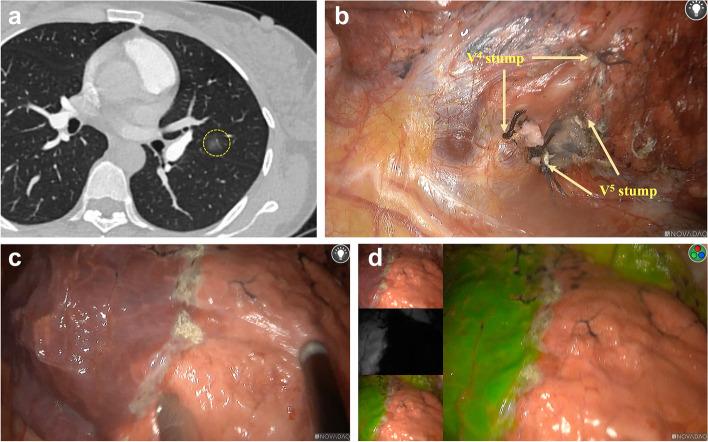

Indocyanine green fluorescence identification of the intersegmental plane by the target segmental vein-first single-blocking during thoracoscopic segmentectomy.

Innovative attempt to explore the feasibility and accuracy of using indocyanine green fluorescence (ICGF) to identify the intersegmental plane by the target segmental veins preferential ligation during thoracoscopic segmentectomy.

A retrospective analysis was conducted on clinical data of 32 consecutive patients who underwent thoracoscopic segmentectomy with intersegmental plane identification using both ICGF and inflation-deflation method after target segmental veins prioritized blocking at Nanjing Chest Hospital from December 2022 to June 2023. Preoperative three-dimensional reconstruction was used to identify the target segment and the anatomical structure of the arteries, veins, and bronchi. After ligating the target segmental veins during surgery, the first intersegmental plane was immediately identified and marked with an electrocoagulation device using an inflation-deflation method. Subsequently, the second intersegmental plane was determined using the ICGF method. Finally, the consistency of the two intersegmental planes was evaluated.

All the 32 patients successfully completed thoracoscopic segmentectomy without ICG-related complications and perioperative death. The average operation time was (98.59 ± 20.72) min, the average intraoperative blood loss was (45.31 ± 35.65) ml, and the average postoperative chest tube removal time was (3.5 ± 1.16) days. The average postoperative hospital stay was (4.66 ± 1.29) days, and the average tumor margin width was (26.96 ± 5.86) mm. The intersegmental plane determined by ICGF method was basically consistent with inflation-deflation method in all patients.

The ICGF can safely and accurately identify the intersegmental plane by target segmental veins preferential ligation during thoracoscopic segmentectomy, which is a beneficial exploration and important supplement to the simplified thoracoscopic anatomical segmentectomy.